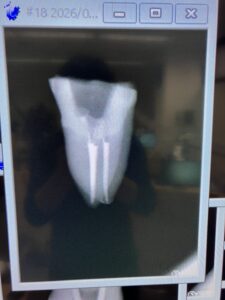

T先生

このセミナーに来て、たまたま大学の同級生のI先生と再会したT先生のテストケースは以下だ。

MB2を探索しようとしてファイルが破折したのでやり直してテストケースを3つも行ったT先生。

いやあ上手いです。

先生も保険でなく、自費で根管治療を行うべき人ですよ。